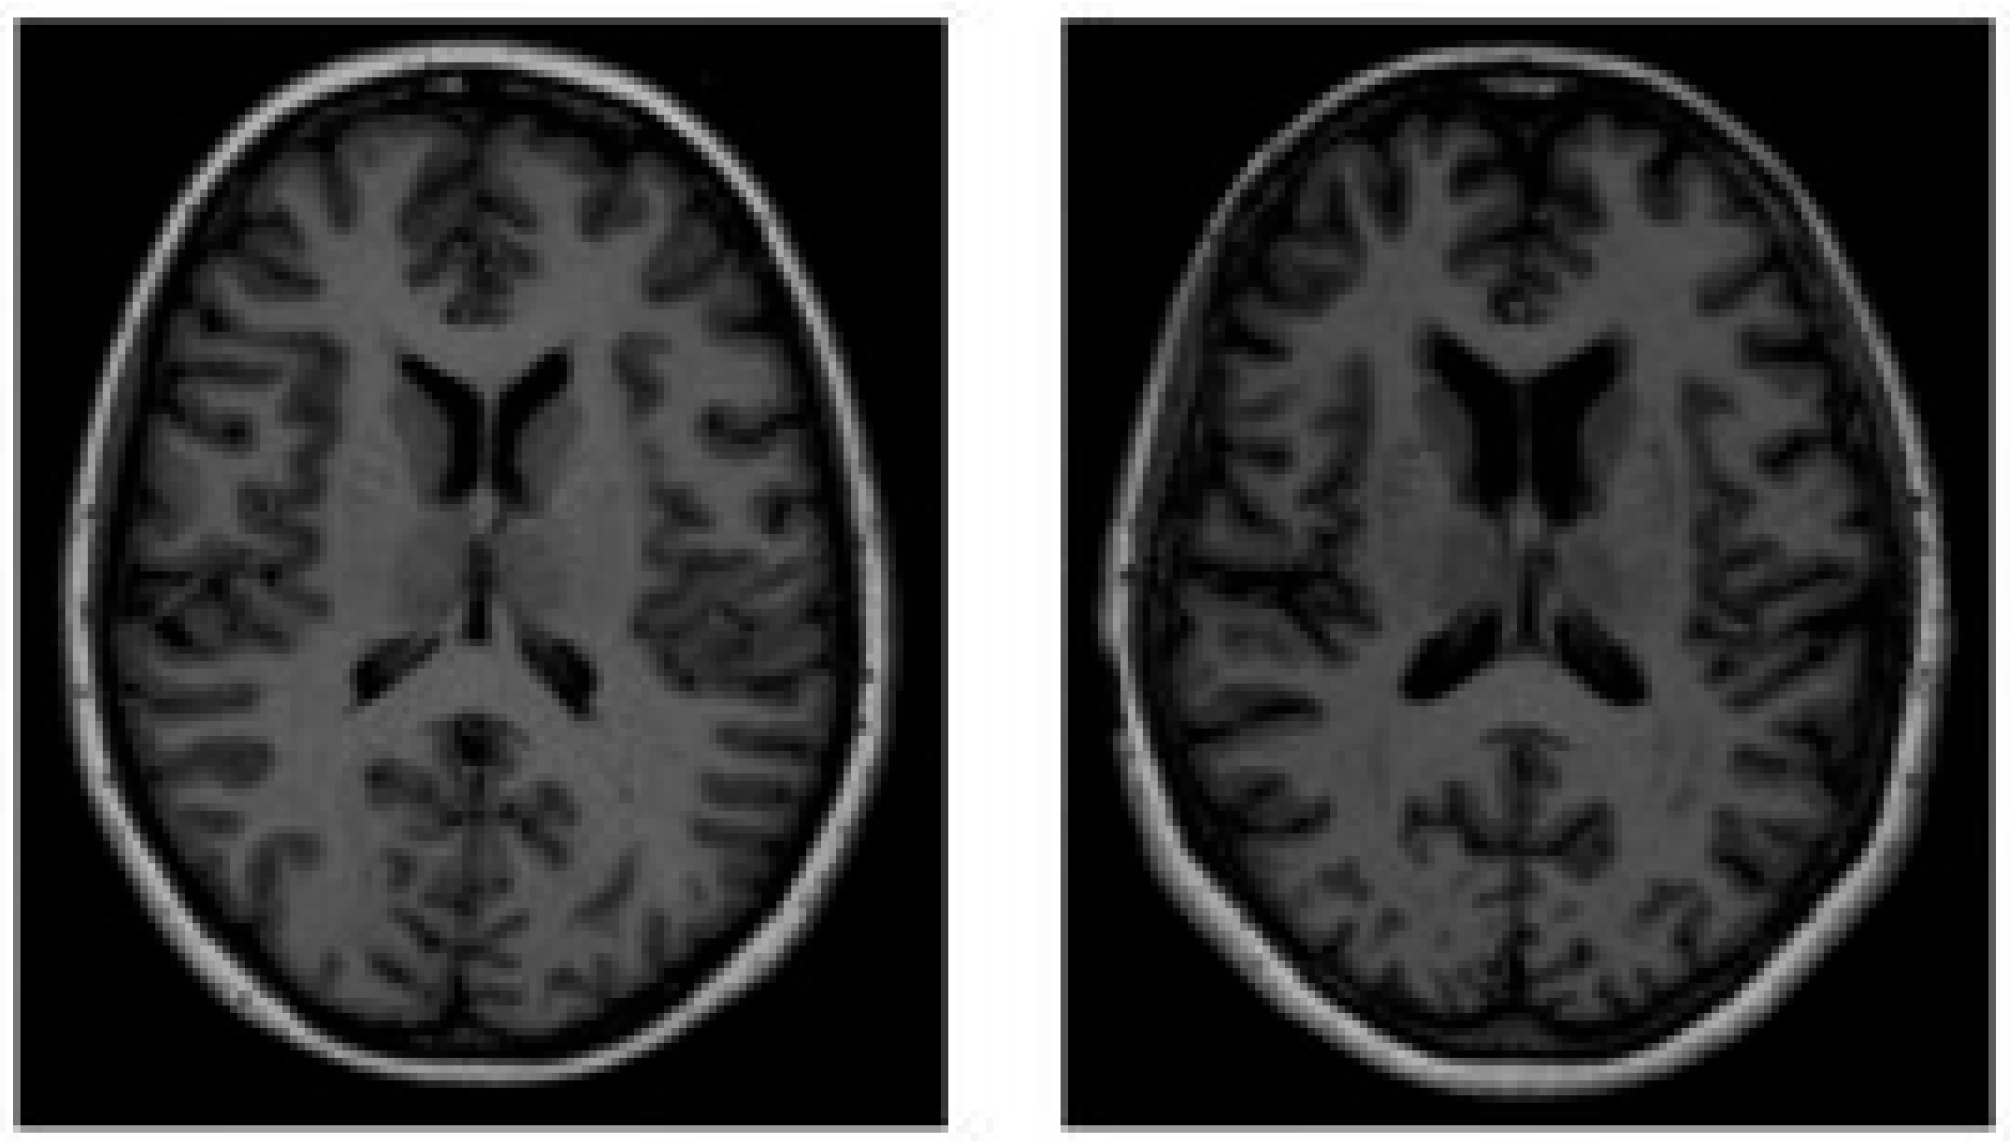

MIRIAD comprises 69 adults (46 AD, 23 CN) scanned up to eight times over 2 years on the same 1.5T system with tightly controlled intervals (weeks to months). Standardized T1 MRI and consistent setup enable precise separation of true atrophy from measurement noise. Publicly released, MIRIAD is used to assess test–retest reliability and minimal detectable change, supporting validation of longitudinal imaging biomarkers [38]. Figure 8 shows some samples of this dataset.

Figure 8. Sample image of the MIRIAD dataset: (a) normal and (b) Alzheimer’s control.